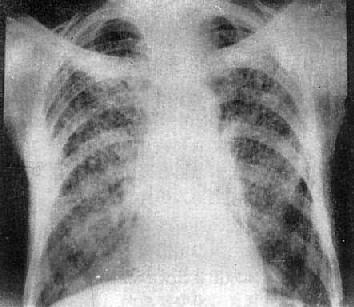

急性粟粒型肺结核

图3-1-22 急性粟粒型肺结核

两肺野布满粟粒状病灶,分布均匀,肺门大